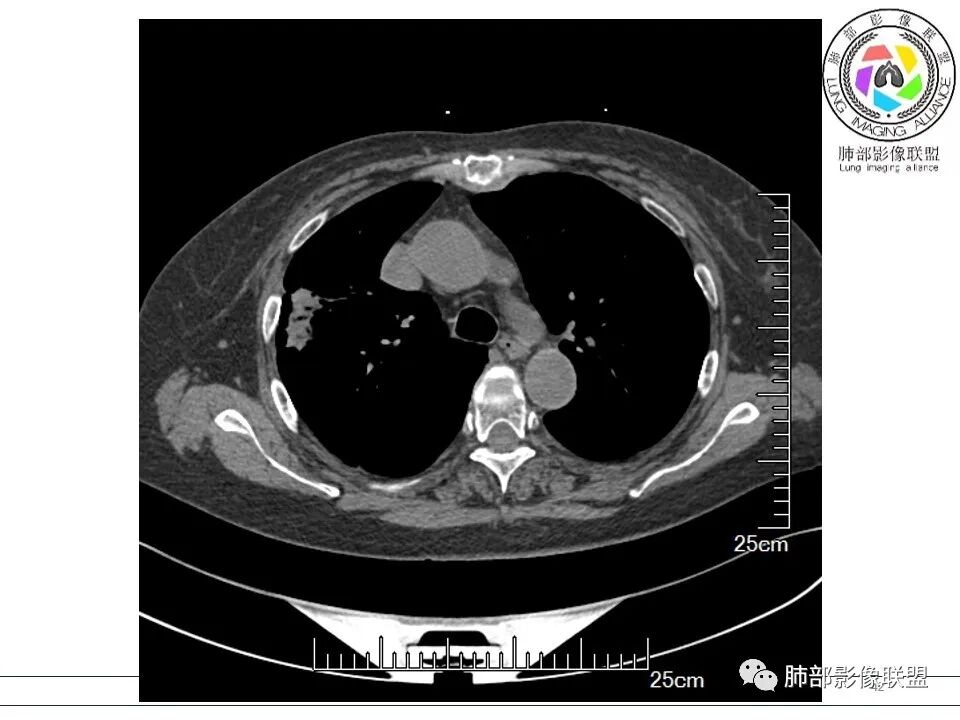

谢加平: 右肺上叶外周,近胸膜下结节病灶,侧向融合,边缘清,见平直边,与胸膜平行分布,支气管进入略扩张,周围见多发长索条影,方向肉芽肿性炎症,建议隐球菌荚膜抗原检查,肿瘤不支持,经皮肺穿刺病理检查!

宇宙: 右肺上叶胸膜下结节,多结节融合,长轴平行胸膜,边缘模糊,周围长索条,胸膜牵拉,近端支气管充气扩张,考虑隐球菌,鉴别OP

黄棘: 右肺上叶近胸膜下病灶,多个融合,边缘清,与胸膜平行分布,支气管进入后堵塞,周围见多发长索条影,考虑隐球菌

果哣.: 右肺上叶靠近胸膜结节影,平直为主,边缘清晰,支气管进入后截断,有扩张,考虑炎性隐球菌可能

衡妈: 老年女性,右肺上叶沿胸膜下不规则实性病灶,长轴平行于胸膜,有结节融合感,边缘部分彭隆部分平直,周围可见数条纤维灶影,病灶内可见充气支气管征未达远端,首诊考虑慢性炎性肉芽肿,隐球菌?机化性肺炎?建议增强扫描及ct下穿刺活检。

放射线 (王秀仙): 右肺上叶胸膜下结节样影,边缘平直收缩,胸膜牵拉,支气管进入病灶并扩张,部分支气管进入后阻塞,长轴平行于胸膜,周围可见片状及条索状影,隐球?机化性肺炎?

张延军: 病变与胸膜平行,近端见气管进入,口服激素治疗史 考虑隐球菌感染 伴OP样改变

晨读:女,70,未诉症状。风湿性多肌痛病史,口服强的松等药物治疗。胸部CT:右肺上叶多发不规则斑片影,沿支气管分布,部分病灶侧向融合、平行于胸膜,边缘平直内收为主、部分彭隆,周围模糊晕、可见数条纤维灶影,胸膜牵拉,病灶内可见充气支气管征、管腔不畅,考虑慢性炎症,PC?OP?鉴别腺Ca、SCLC等。

良孑: 右肺胸膜下多发结节,长轴与胸膜平行,部分病灶有多结节融合,可见近端支气管充气征,有晕征及晕中软毛刺,长期口服激素病史,抗炎效果欠佳。病灶形态单一,无播散性树芽,结节内无支气管穿行,单侧发病,收缩力差,可排除TB,OP及淋巴瘤,综和考虑支持隐球菌